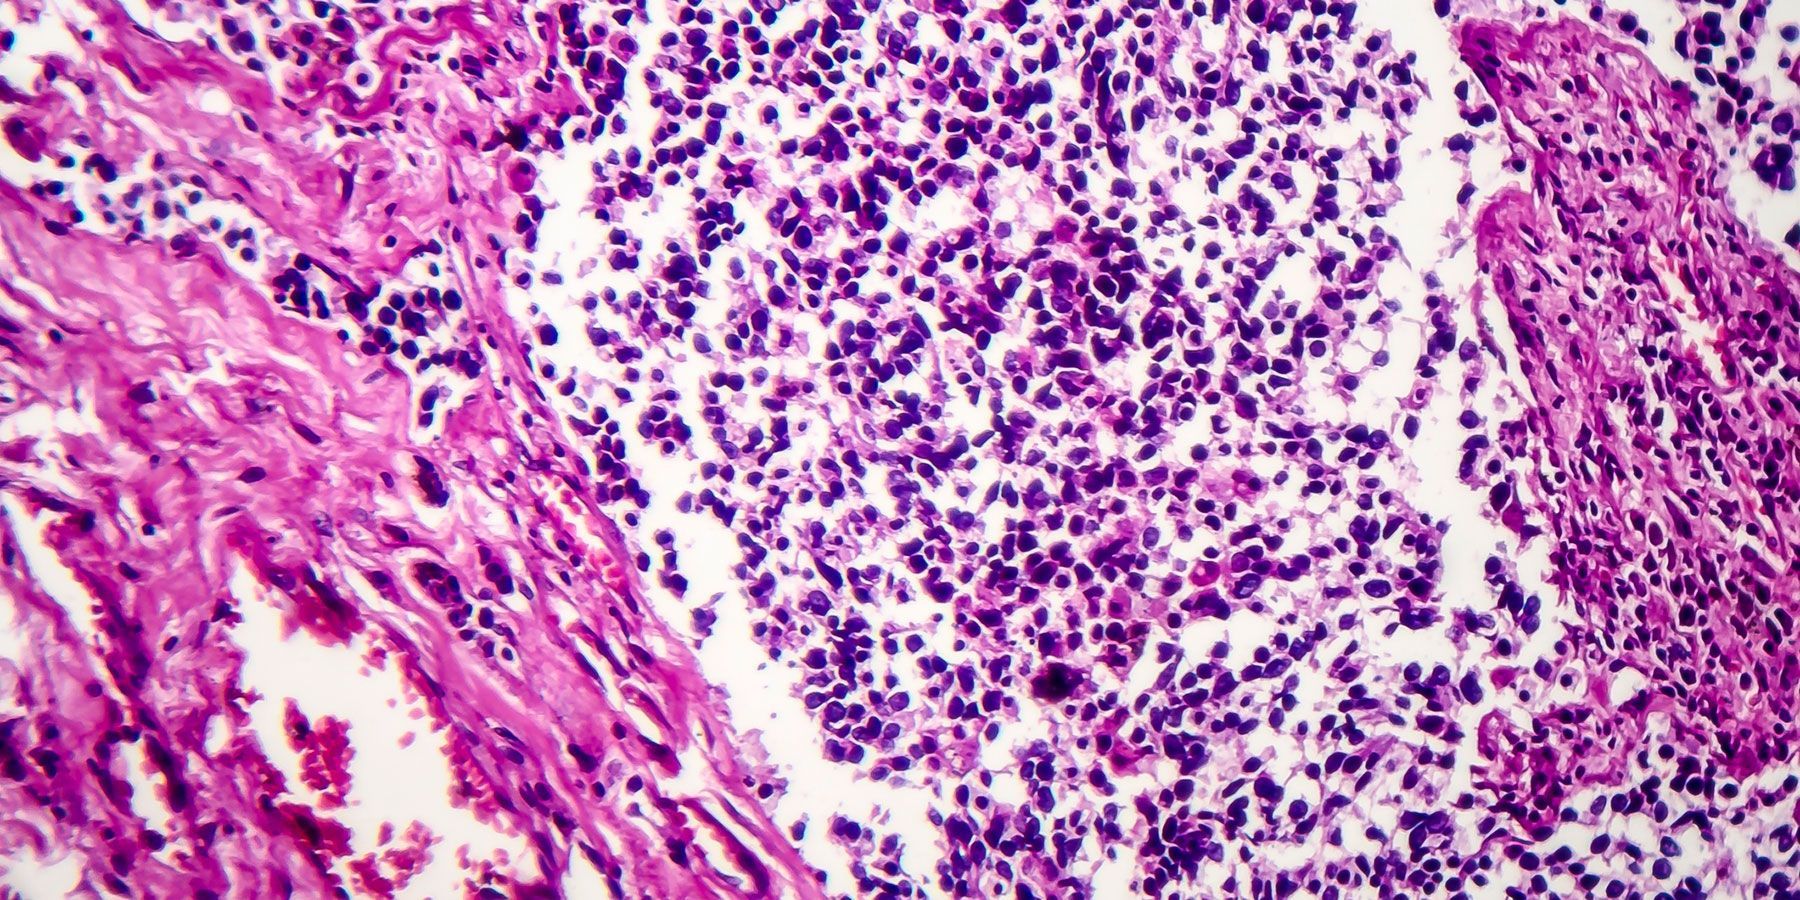

Non-small-cell lung cancer accounts for more than 80 percent of all lung cancers. Cases of lung cancer in people who have never smoked are usually non-small cell lung cancer. The disease affects more women than men. Standard treatment for non-small cell lung cancer is a combination of surgery, chemotherapy, and radiotherapy, with no targeted therapy option. Patients with advanced non-small cell lung cancer have poor prognosis with median overall survival rate of 12 months (Toh et al. Annals academy Singapore 2017)